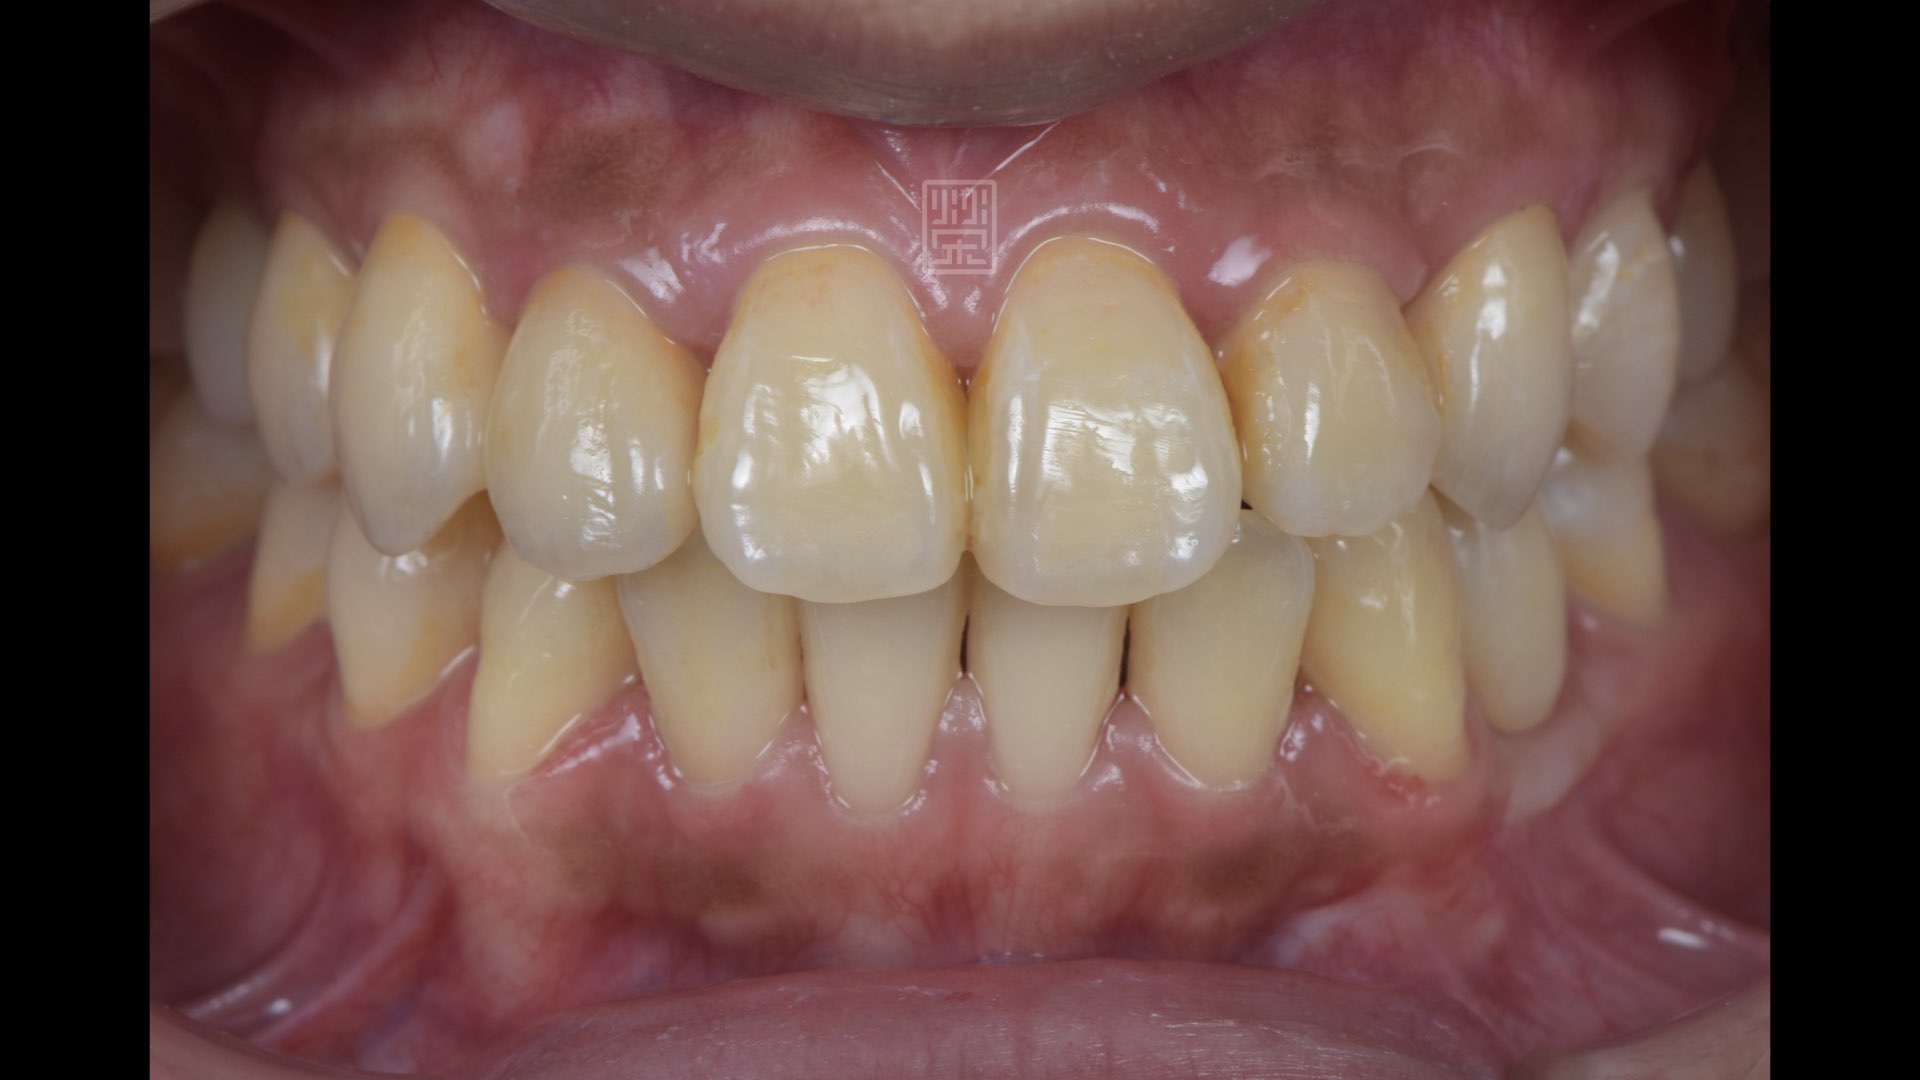

全瓷冠完成,是哪顆呢?

全瓷冠、植牙修復完成